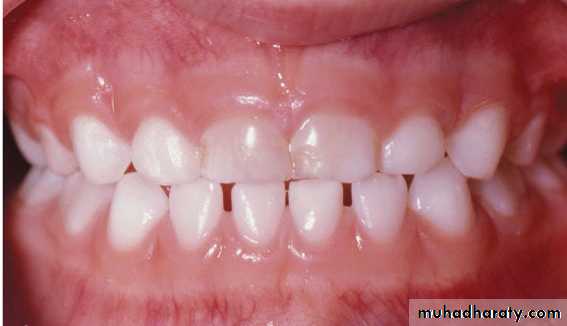

• In the majority of children with unilateral posterior crossbite there is moderate bilateral narrowing of the upper arch leading to posterior interferences upon closure. This forces the mandible to shift to a new position for maximum intercuspation.Initial contact

Centric occlusion